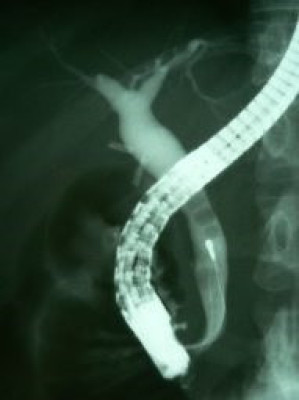

Coledocolitiasis con antecedente de colecistectomía por laparoscopía

Envíado por Dr. Carlos Miguel Zavaleta Consuegra